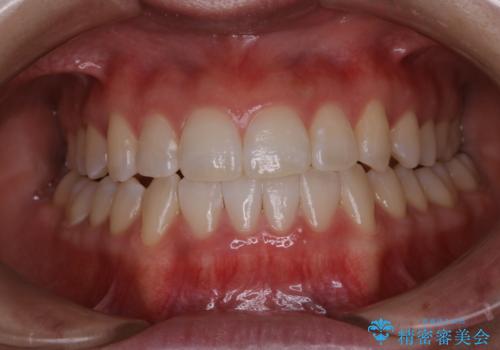

上下のガタガタのマウスピースによる非抜歯矯正